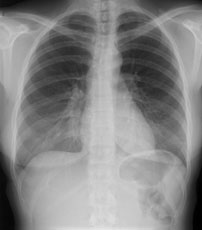

Eine 36-jährige Patientin kommt zu Ihnen in die Praxis. Sie berichtet über einen grippalen, fieberhaften Infekt, seit einer Woche bestehend.

In der Lungenauskultation sind Rasselgeräusche beidseits basal zu hören. Bei einem CRP von 160 mg/l veranlassen Sie ein Thoraxröntgen mit der Frage nach Infiltrat.

Hier sehen Sie die Bilder:

Thorax pa

Wie lautet Ihre Diagnose?